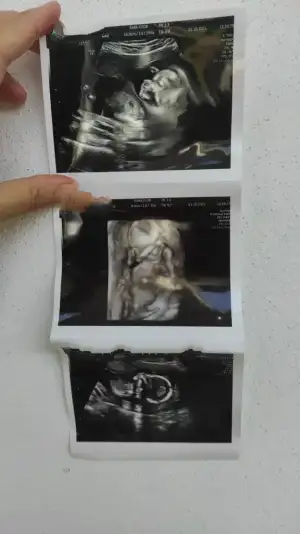

Kızlar benim de bugündü kontrolüm. 11+5 de nub a göre kız demişti tuttu valla kesin artık kız olduğu

Çok hareketliydi eli kolu ayakları hiç durmuyor anası gibi kurtlu olacak belli

AFP yaptır dedi haftaya laboratuvarda yaptırıcam klinikte yapılınca sigortam karşılamıyor çünkü. Tüm organları tek tek detaylıca inceledik. Suyu, omurgası vs. İyi dedi. Genel olarak olması gerektiği gibi dedi :) Ay ultrason fotoğrafında da aynı eşime benzettim

Eşim de aynı anası demek ki babaanneye benzeyecek

Tetanoz için arayacaklar sağlık ocağından benim için yaptırmanın bir mahsuru yok dedi. Parmak uçlarımda soyulma oldu bi de benim. Vejetaryen olduğumu biliyo demir eksikliği olabilir dedi ona da bakılacak haftaya. Her gün mutlaka 1 yumurta ye bir öğününde de mutlaka baklagil olsun dedi protein için. Sağlık ocağı demir ilacı vermişti vagaferon diye bi şey ona artık başla dedi. 15-16 cm 133 Gr mış minik KV'm